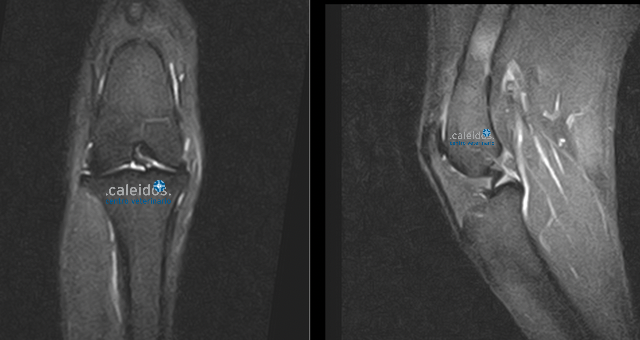

At Caleidos clinic we also do MRI of knee joints, a method that is not very widespread in the veterinary field.